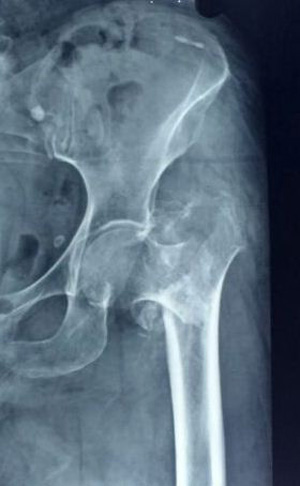

A 70 year old male with unstable fracture pattern was submitted to osteosynthesis with PFN. The fracture was classified as AO/OTA type 31A2.3 (Figure 6a). Immediate post-operative radiograph of the patient revealed relatively unstable fracture fixation because of loss of antero-medial buttress, superior placement of hip screws, almost same level of screw tips of both lag and derotation screw (Figure 6b). Because of relatively unstable fracture fixation, patient was advised delayed weight bearing. At home, patient started weight bearing with aid of walking frame. At 3 months post-operative, the patient evolved with varus collapse and differential migration of the hip screws, with the caudal one migrating laterally (typical of the Z-effect, Figure 6c). Patient was offered for removal of derotation screw. Patient refused for any surgical intervention as he was up and about with walker with minimal pain.

Figure 6b Immediate post-operative radiograph showing loss of antero-medial buttress (arrows). Also note the superior placement of hip screws & almost same level of screw tips of both lag and derotation screw.

Figure 6c Three months post-operative radiograph showing varus collapse (small arrow) and differential migration of the hip screws (long arrow), with the caudal one migrating laterally (typical of the Z-effect).